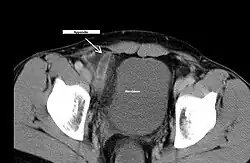

- Computertomographie (CT)

Akute Blinddarmentzündung im CT.

Akute Blinddarmentzündung im CT.